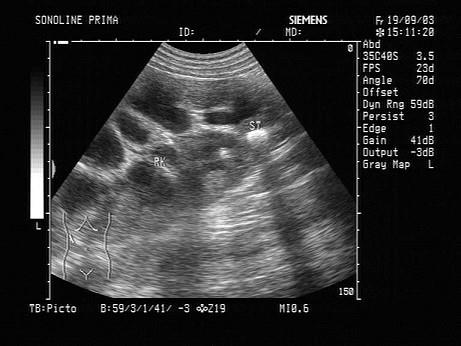

根据超声图像,该病例最可能诊断是?(?)A.肾结石B.肾感染C.肾结石并肾积水、感染D.肾积水E.肾囊肿

问题 根据超声图像,该病例最可能诊断是?(?)

选项 A.肾结石 B.肾感染 C.肾结石并肾积水、感染 D.肾积水 E.肾囊肿

答案 C